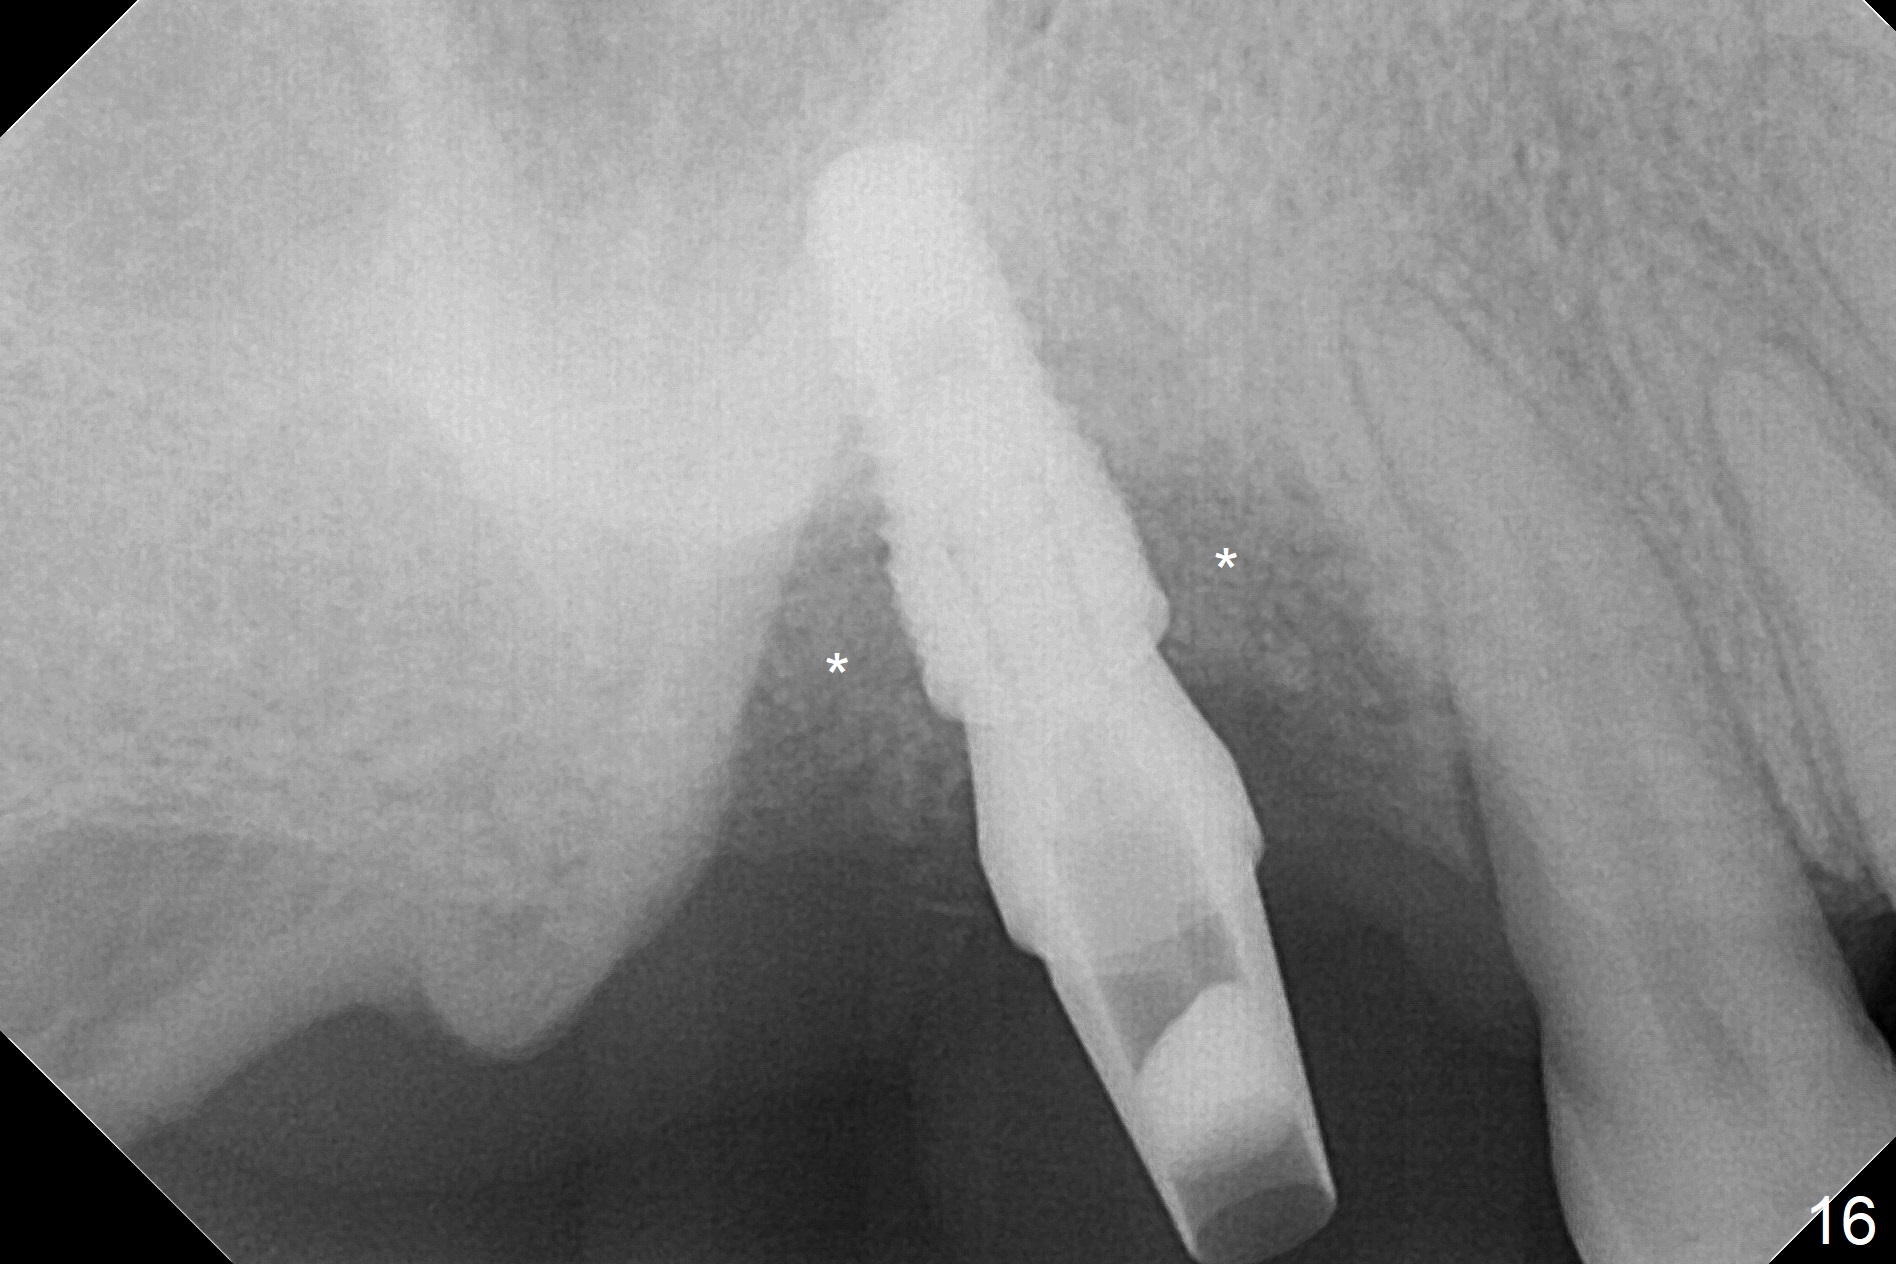

Two weeks later, the buccal gingiva appears to have grown downward (Fig.13). Fig.14 is taken when the provisional is removed. To facilitate this process, change abutment from 4.8x7(3) to (4.5) mm and a new provisional is fabricated (Fig.15): note the metal exposure distobuccally. When the patient returns in another two week, the gap should be able to disappear. There is no loss of bone graft 3 months postop (Fig.16). Two weeks later (3.5 months postop), the margin of the abutment is supragingival buccally and subgingival palatally (Fig.17,18). The gingiva seems to have migrated downward (Fig.19 arrow), while the bone density around the coronal implant appears to increase 5.5 months post cementation (Fig.20). There is buccal swelling with purulent discharge 1.5 years post cementation (Fig.21). Perimplantitis develops. Tuberosis bone graft will be performed when the limited ortho is finished.